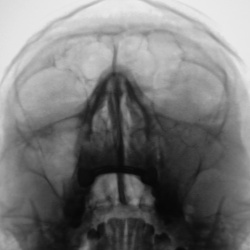

Пациент направлен отоларингологом на рентгенографию ППН.Ваше мнение уважаемые коллеги?